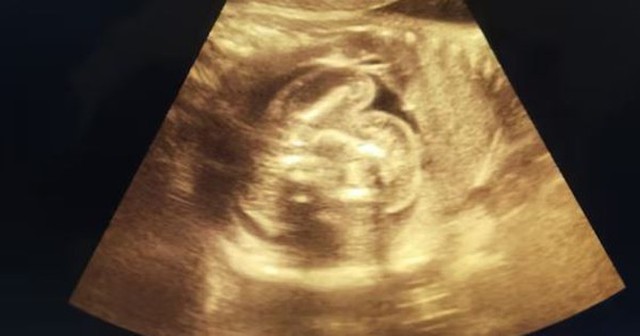

Khi siêu âm cho bé trai sơ sinh, các bác sĩ đã vô cùng sửng sốt.

Vào ngày 23/9, cô đã sinh một bé trai khỏe mạnh. Tuy nhiên, bác sĩ sản phụ khoa và bác sĩ phẫu thuật đã phát hiện ra em bé có điều bất thường. Siêu âm cho thấy một thai nhi có tủy sống trong bụng em bé.

Theo các bác sĩ, bé trai mắc phải một tình trạng y khoa cực kỳ hiếm gặp được gọi là "thai trong thai".